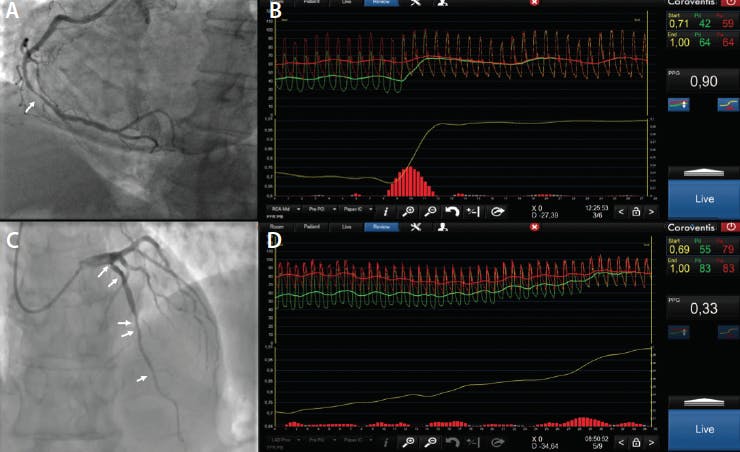

The characterization of focal or diffuse epicardial disease has been commonly done using conventional angiography. Based on coronary angiograms, different definitions have been proposed aiming at differentiating diffuse and focal CAD.9,10 However, assessing the pattern of atherosclerosis using angiography is often equivocal and has low interobserver reproducibility.11 Moreover, studies using intravascular ultrasound have demonstrated diffuse atherosclerosis even in normal angiographic segments.12,13 An alternative approach to estimate the degree of diffuseness of CAD is coronary physiology using intracoronary pressure pullbacks. Pullback curves depict the distribution of epicardial resistance and expose the functional pattern of CAD. Furthermore, a pullback maneuver identifies the location of pressure step-ups in the coronary vessel as targets for PCI (Figure 1).14

Figure 1. Morphologic and functional CAD pattern evaluation. Coronary angiography showing a right coronary artery (RCA) with angiographically focal lesion (white arrow) (A). FFR pullback of the RCA showing a focal pattern of CAD with a PPG of 0.90 (B). Coronary angiography showing a left anterior descendent artery (LAD) with diffuse lesions (white arrows) (C). FFR pullback of the LAD showing a diffuse pattern with a PPG of 0.33 (D).